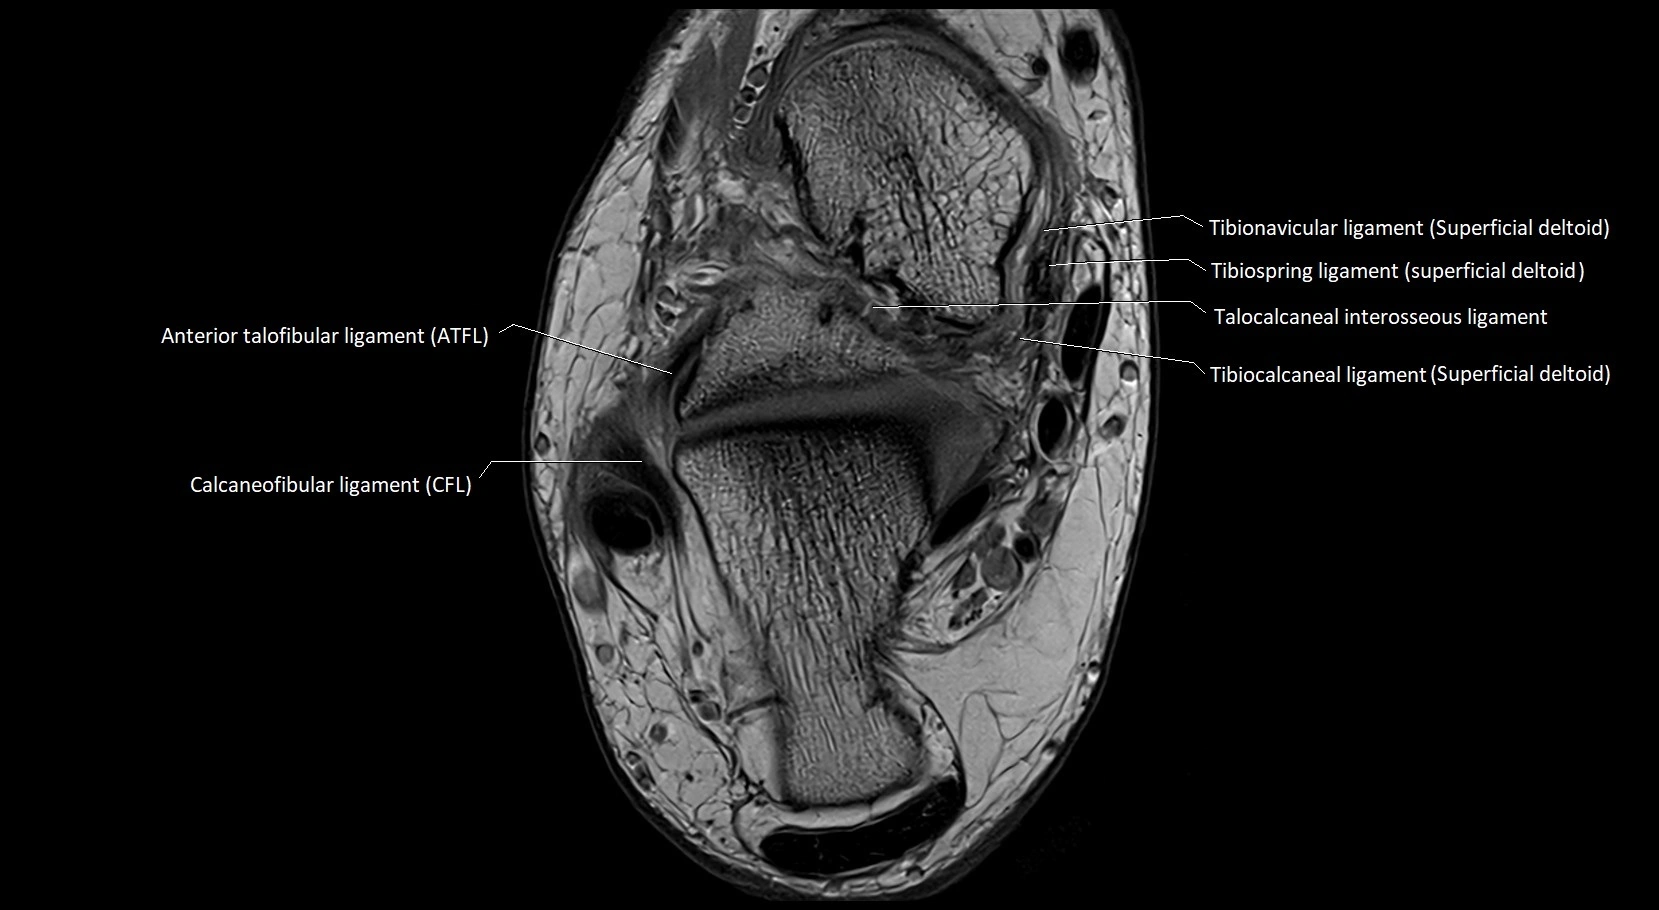

MRI image

image